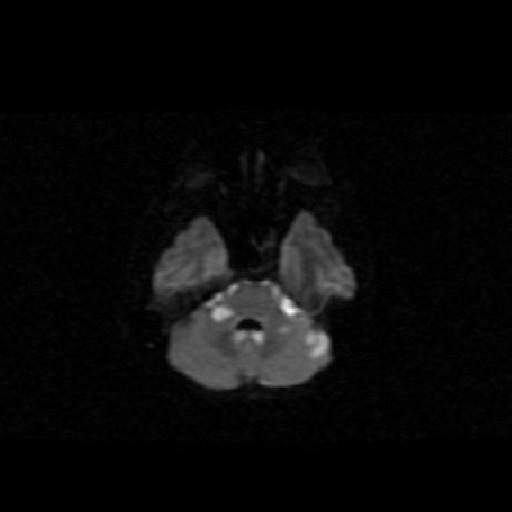

We report a fatal case of meningitis, caused by Fusobacterium necrophorum, secondary to otitis media in an alcoholic male. Diagnosis was delayed due to the typical slow growth of the organism. The clinical course was complicated by encephalitis and by hydrocephalus. The patient failed to respond to metronidazole and penicillin. The patient died on day 12 from increased intracranial pressure and brain stem infarction.

我们报告一例由坏死梭杆菌引起的致命性脑膜炎病例,该病例继发于一名酗酒男性的中耳炎。由于该病菌典型的缓慢生长特性,诊断被延误。临床过程因脑炎和脑积水而复杂化。患者对甲硝唑和青霉素治疗无反应。患者于第12天因颅内压升高和脑干梗死死亡。